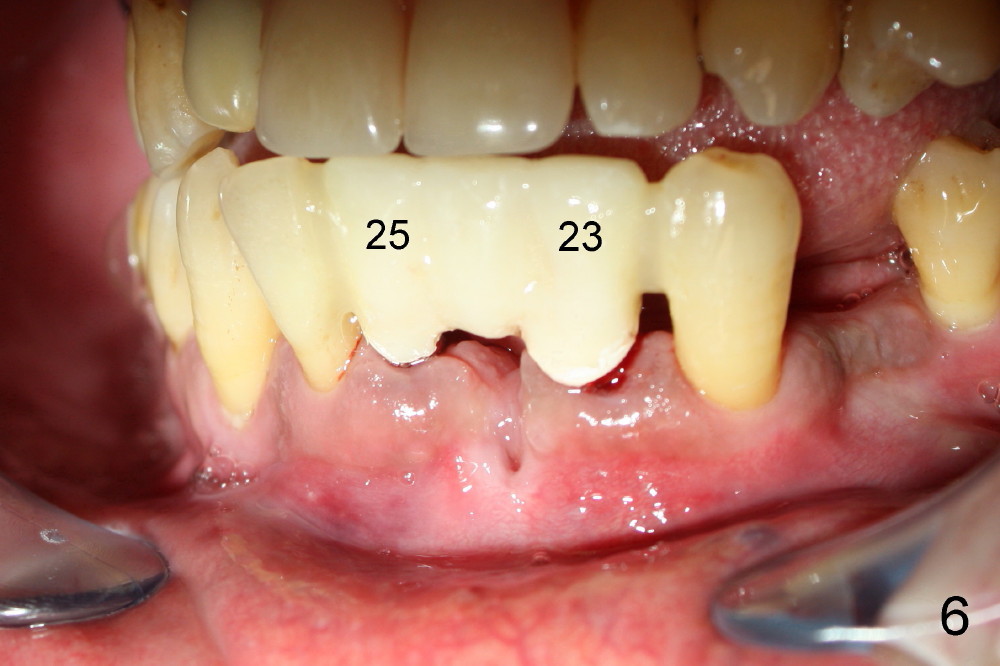

Dear Drs. Dunson and Borgner: Thank you for giving me invaluable advice, which I will use for future cases. In fact the teeth #23 and 25 were extracted last Thursday. The mesiodistal width of both roots is 3.5 mm, while the buccolingual 5 mm. It is presumed that a 4 mm implant should not perforate the buccal plate. On the other hand, the relatively large implant should fill most of the socket. Upon implant placement, the buccal plate does not feel to bulge or perforation, particularly in apical aspect, by tactile sensation. There is separation between the root of the tooth #22 and the pilot drill (1.5 mm) at the site of #23 whereas the space is limited between the pilot drill (2 mm) at the site of #25 and the root of the tooth #26. As Fig.4 and 5 indicate, a 4x17 mm one-piece implant is placed at the site of #23 and 3.5x17 mm at #25. A temporary bridge is fabricated between #23 and 25 and splinted to #22 and 27 (Fig.6). Since the abutment of the 4x17 mm one-piece implant is not tall, parallelism is not an issue after initial prep. The tooth #21 is missing. Do we still have to splint between #20 and #29 in one piece lingually?